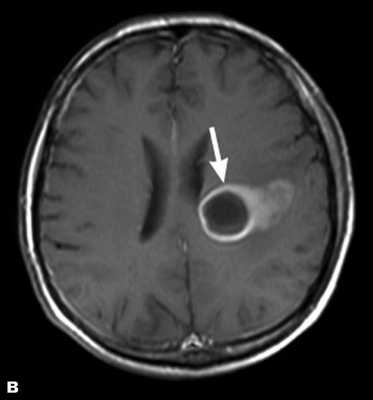

Доброкачественные опухоли чаще всего характеризуются однородной структурой, из-за экспансивного роста имеют четкие, ровные контуры, вокруг таких новообразований отсутствует перифокальный отек. Кроме того, доброкачественные образования не накапливают или слабо накапливают контрастирующий препарат.

Злокачественная опухоль на МРТ

Злокачественные опухоли характеризуются инвазивностью, то есть врастанием в здоровые ткани, поэтому контуры таких образований нечеткие и неровные, а потому достоверно определять границы таких опухолей довольно сложно. Кроме того, структура злокачественной опухоли часто бывает неоднородна за счет распада (некроза), кровоизлияния и коллоидной дегенерации. Вокруг злокачественной опухоли, как правило, выявляется выраженный перифокальный отек, который может приводить к смещению срединных структур головного мозга и появлению аксиальной дислокации. Также могут быть выявлены признаки метастазирования.